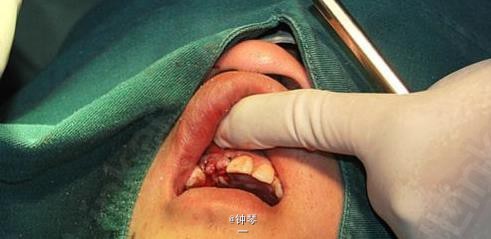

前牙种植+钛网应用

患者,女,30岁,右上1,2缺失要求种植。平素体质一般,否认高血压、糖尿病及心脏病史,否认肝炎、结核病史,无药物、食物过敏史,无外伤、手术及输血史。